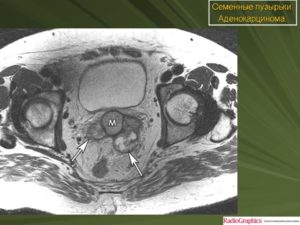

Для диагностики чаще применяют ТРУЗИ (трансректальное ультразвуковое исследование). Если есть подозрение на злокачественный процесс, выполняют магнитно-резонансную томографию, позволяющую дать оценку отношению кисты (опухоли) к близлежащим тканям.

МРТ — более информативный метод, но учитывая его высокую стоимость, к магнитно-резонансной томографии прибегают только при подозрении на рак простаты.